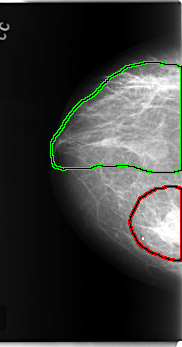

C_0189_1.RIGHT_MLO

FILE: C_0189_1.RIGHT_MLO.OVERLAY

TOTAL_ABNORMALITIES 3

ABNORMALITY 1

LESION_TYPE CALCIFICATION TYPE PLEOMORPHIC DISTRIBUTION CLUSTERED

LESION_TYPE MASS SHAPE ROUND MARGINS CIRCUMSCRIBED

ASSESSMENT 5

SUBTLETY 5

PATHOLOGY MALIGNANT

TOTAL_OUTLINES 1

ABNORMALITY 2

LESION_TYPE CALCIFICATION TYPE PLEOMORPHIC DISTRIBUTION REGIONAL

ABNORMALITY 3